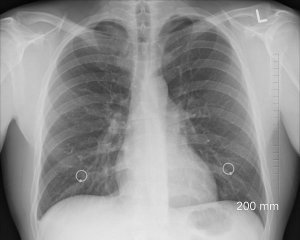

В клинике Университетского колледжа Лондона ученые провели КТ 12,1 тыс. людям, которые курят или бросили курить. У 180 из них обнаружили рак легких, при этом 70% случаев зафиксированы на первых двух стадиях заболевания.

На КТ-сканирования пациентов с подозрением на рак легких направляют только после рентгеновского сканирования, где не всегда можно отличить раковую опухоль от других патологий.